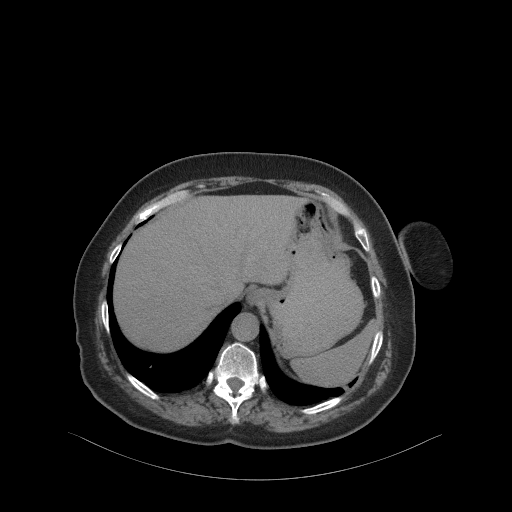

Reconstructed NATIVE CT scan (cycle consistency)

No window - Raw intensity values

Lung window (WL -600, WW 1500 β†’ Low βˆ’1350, High +150)

Mediastinum window (WL 40, WW 400 β†’ Low βˆ’160, High +240)